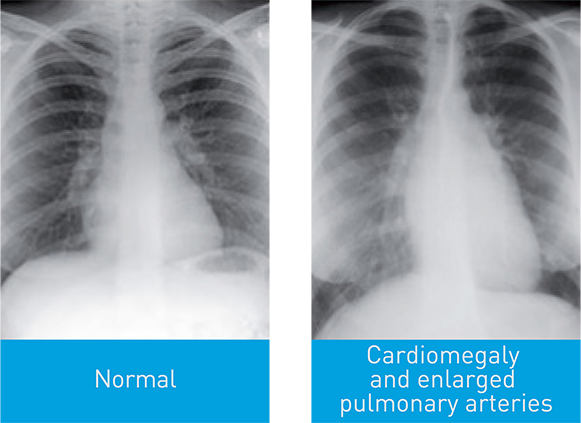

When PAH is suspected, clinical history, symptoms, signs, electrocardiogram (ECG), chest radiograph, echocardiogram, PFTs, CT of the chest and a V/Q scan are all required in order to exclude diagnosis of left heart disease, lung disease or chronic thromboembolic pulmonary hypertension (CTEPH). To confirm diagnosis of PAH, referral to a PH specialist centre for Right Heart Catheterization is required.3

There are several other key investigations you can perform to raise suspicion of PH and help identify and classify its cause. Note that right heart catheterisation (RHC) is required to confirm a diagnosis of PAH, and should be performed by a PH centre.3